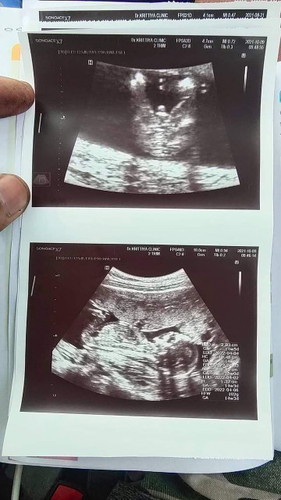

ท้องแรก 14W 3d น้องหนัก 102 กรัม ตอนนี้รู้เพศน้องแล้วค่ะ หมอบอก75%เป็นผู้ชายค่ะ #ท้องแรกคะ